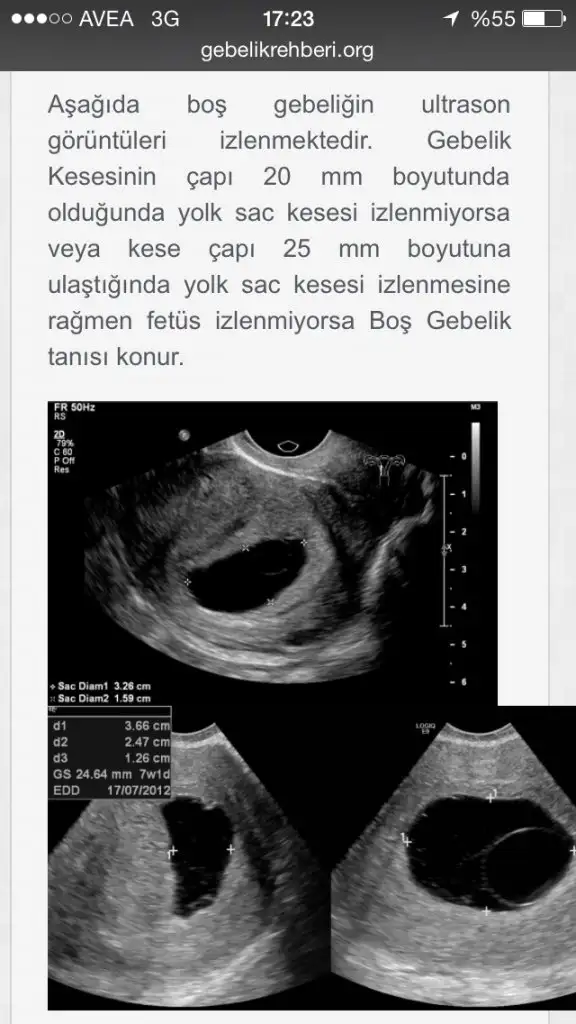

CNmboş gebelikte kese var ama için de embriyo yok zaten kalp atışı da olmuyor hcg artıyor ama yeterli değil üstteki boş gebelik alttaki sağlıklıboş gebelik nasıl oluyor canım ya...inşallah bir daha olmaz...geçmiş olsun..

SAĞDAKİ GİBİ SAĞLIKLI GEBELİKLERİMİZ OLSUNN İNŞA EN KISA ZAMANDACNmboş gebelikte kese var ama için de embriyo yok zaten kalp atışı da olmuyor hcg artıyor ama yeterli değil üstteki boş gebelik alttaki sağlıklı